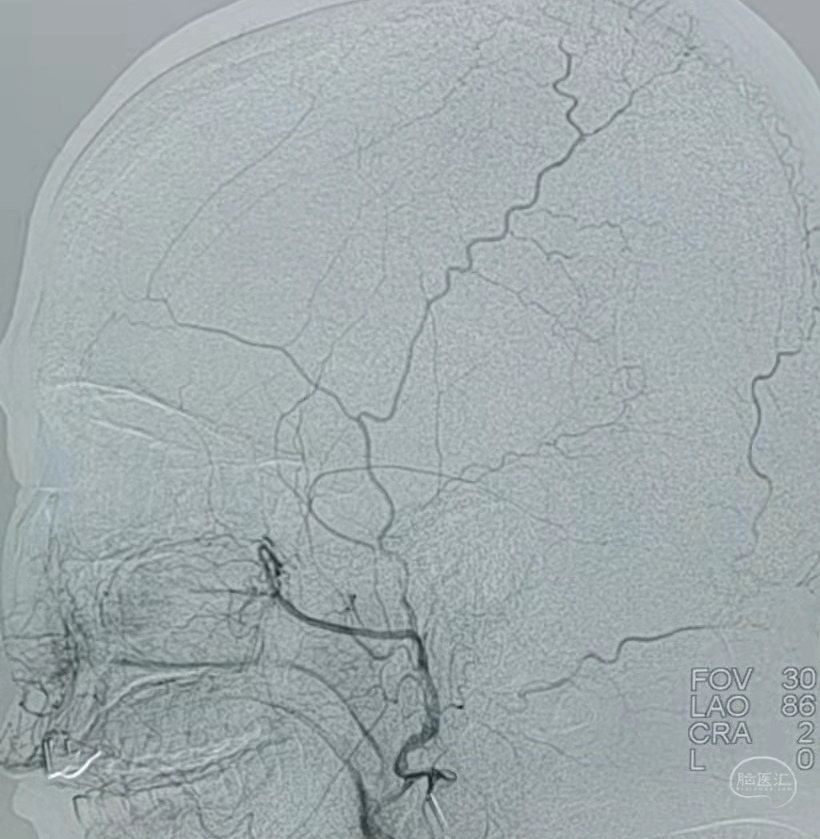

DSA:左侧颈内动脉闭塞。

颞浅动脉未向颅内代偿。

DSA:右侧大脑中动脉、大脑前动脉闭塞,烟雾样血管形成。

颞浅动脉未向颅内代偿。

DSA:左侧大脑中动脉、大脑前动脉闭塞,烟雾样血管形成。

颞浅动脉未向颅内代偿。